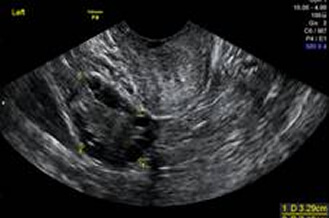

卵巢巧克力囊腫